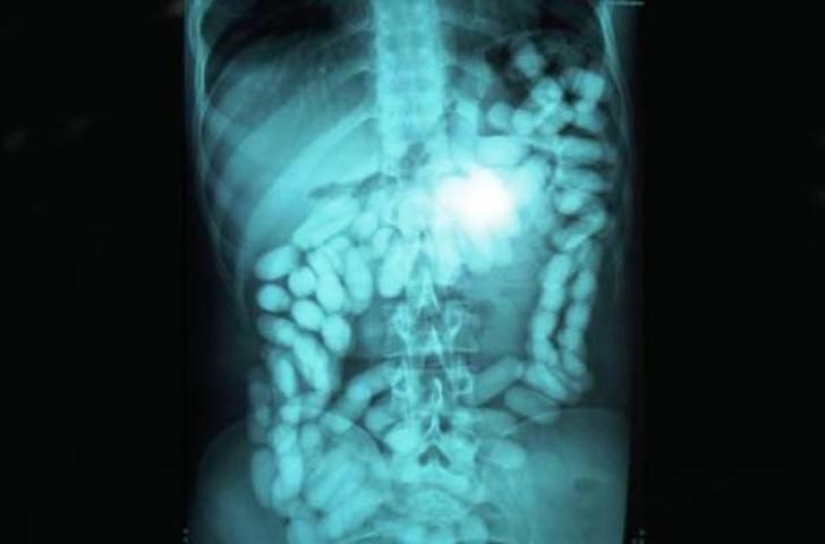

methamphetamines.